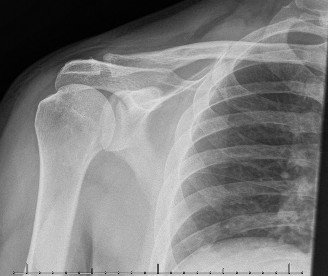

CASE 11 A 33-year-old male presents to the ED after a fall during a soccer game. He reports significant right shoulder pain and limited ROM. An x-ray taken in the ED is shown below (Fig. 2–29).

Figure 2–29

The correct answer is (A). The ED image shown in Figure 2–29 includes only an AP view of the right shoulder. In the setting of an acute injury and pain, technicians may be hesitant to obtain additional views. A single view, however, is insufficient to diagnose either a fracture, as orthogonal views are required, or a shoulder dislocation which is best seen on an axillary view (see Fig. 2–30). Answers B and C are inappropriate as a diagnosis has not been established yet and a dislocation or fracture must be conclusively ruled out. Answers D and E may be options that are exercised in the clinic but do not represent the next step in the management of this patient.